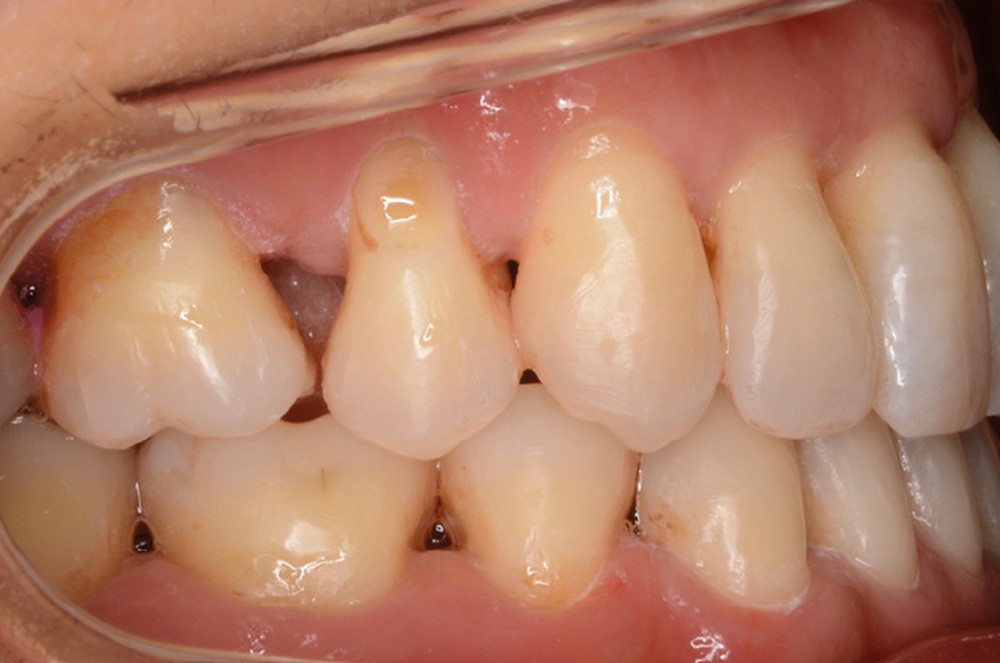

Sur le plan squelettique, on retrouve une classe III de Ballard par hypomaxillie, dans un schéma facial hyperdivergent.

Sur le plan dentaire, la patiente est en classe III droite et gauche, canine et molaire de 6 mm, avec une occlusion inversée antérieure localisée à 11, 12 et 22. Elle présente une dysharmonie dents-arcades sévère, une agénésie d’une incisive mandibulaire est à signaler, et les troisièmes molaires ont été extraites à l’âge de 21 ans.

Au niveau fonctionnel, on note un bruxisme statique avec contact permanent entre les dents maxillaires et mandibulaires. La patiente présente des prématurités en relation centrée sur les incisives, le guidage en propulsion est perturbé et des interférences multiples sont retrouvées en latéralités droite et gauche.